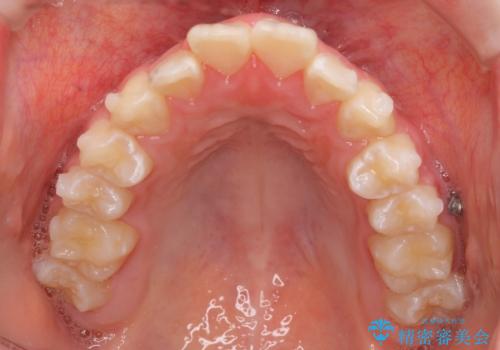

中学生のマウスピース矯正 歯を抜かずにキレイに

- 出っ歯を主訴に来院。

(1)インビザラインで歯を少し削って並べる。歯は抜かない。・・・歯を抜かなくて良い。歯磨きが楽、装置も目立たない。通院は3ヶ月に1回。

非抜歯ながらも、矯正用のインプラントを使用し、出来るだけ前歯を下げるように工夫して治療しました。

治療結果にはお母様、ご本人も含め、大変喜んでいただきました。

歯を抜かずに治療しましたが、治療前後で口元が悪化しないように治療することができました。